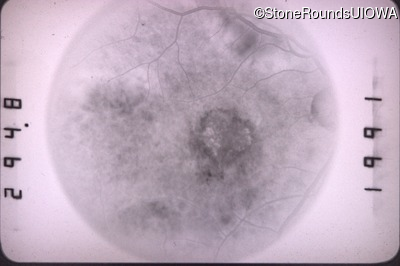

Fluorescein Angiography - Right - 20/100 -1

Exemplar

Fluorescein Angiography - Left - 20/40 -1